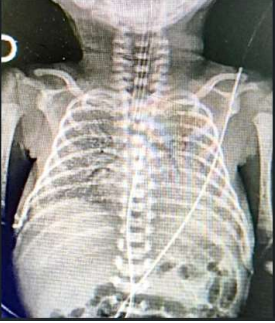

RN nasceu de parto vaginal, com APGAR 5 e 6, apresentando desconforto respiratório de imediato, caracterizado por gemência, tiragem subcostal e taquipneia. A idade gestacional pela DUM foi de 31 semanas. RN foi levado à UTI neonatal, com piora importante do desconforto respiratório, necessitando de intubação orotraqueal. Neonatologista solicitou RX de tórax (imagem abaixo).